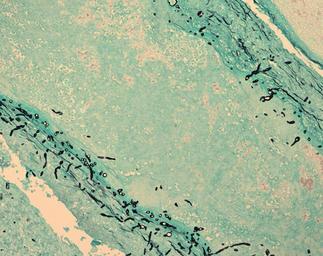

Keywords: Dpk-meningitis-fungus-in-brain.jpg On a page about the w New England Compounding Center meningitis outbreak the caption of this picture on the CDC web site says http //www cdc gov/media/releases/2012/dpk-meningitis-photos html Special stains were used for microscopic examination of brain tissue from patients with clinical cases of meningitis The black objects seen in these images is fungus Provenance Picture retrieved on 2012-11-21 This picture on the CDC website is linked from the digital press kit page of the fungal meningitis outbreak page http //www cdc gov/media/releases/2012/dpk-meningitis-photos html Other pictures on this page are also in the CDC PHIL database http //phil cdc gov/phil/home asp and have similar metadata as this picture I cannot find this specific picture on the PHIL database but it is probably there somewhere Those other pictures are explicitly labeled as being in the public domain This picture is explicitly in the press kit implying authorization to copy This picture is on the US government CDC web site and is not marked as not being in the public domain PD-USGov Central nervous system fungal infections Uploaded with UploadWizard Meningitis Taken with Zeiss AxioCam HR